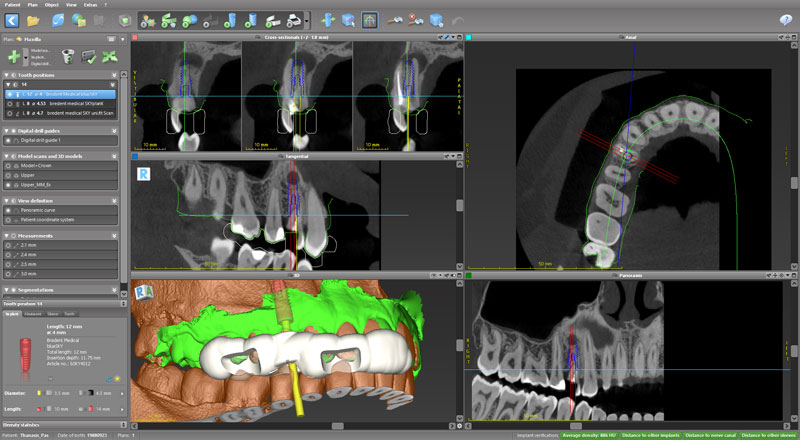

Ψηφιακό πλάνο θεραπείας

Κατευθυνόμενη τοποθέτηση εμφυτευμάτων

Σχεδιασμός χειρουργικού οδηγού

Πρακτική άσκηση: ο κάθε συμμετέχων θα σχεδιάσει σε ειδικό λογισμικό έναν χειρουργικό οδηγό

- Ψηφιακό πλάνο θεραπείας

- Κατευθυνόμενη τοποθέτηση εμφυτευμάτων

- Σχεδιασμός χειρουργικού οδηγού

- Πρακτική άσκηση: ο κάθε συμμετέχων θα σχεδιάσει σε ειδικό λογισμικό έναν χειρουργικό οδηγό